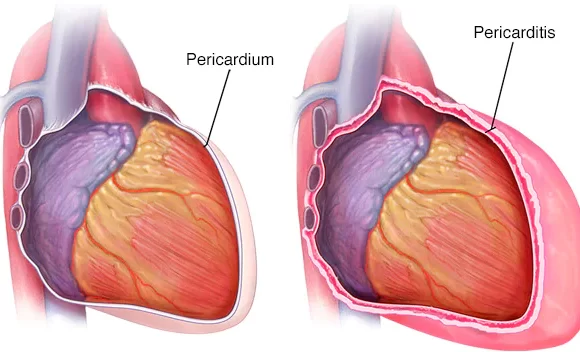

التهاب التامور الحاد هو التهاب يصيب التأمور (الكيس المرن ذو الطبقتين الذي يغلف القلب) الذي يبدأ فجأة ، وغالبًا ما يكون مؤلمًا ، ويسبب دخول السوائل ومكونات الدم مثل الفيبرين وخلايا الدم الحمراء وخلايا الدم البيضاء إلى الحيز التأموري .

في بعض الأحيان ، يمكن أن يتسبب الالتهاب في دخول السوائل الزائدة إلى الحيز التأموري (الانصباب التامور). في بعض الأحيان ، عندما يكون التهاب التامور ناتجًا عن إصابة أو سرطان أو جراحة في القلب ، يكون السائل عبارة عن دم.